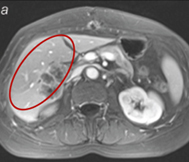

Ядрено-магнитен резонанс преди лечението

ЯМР след 30-дневен курс